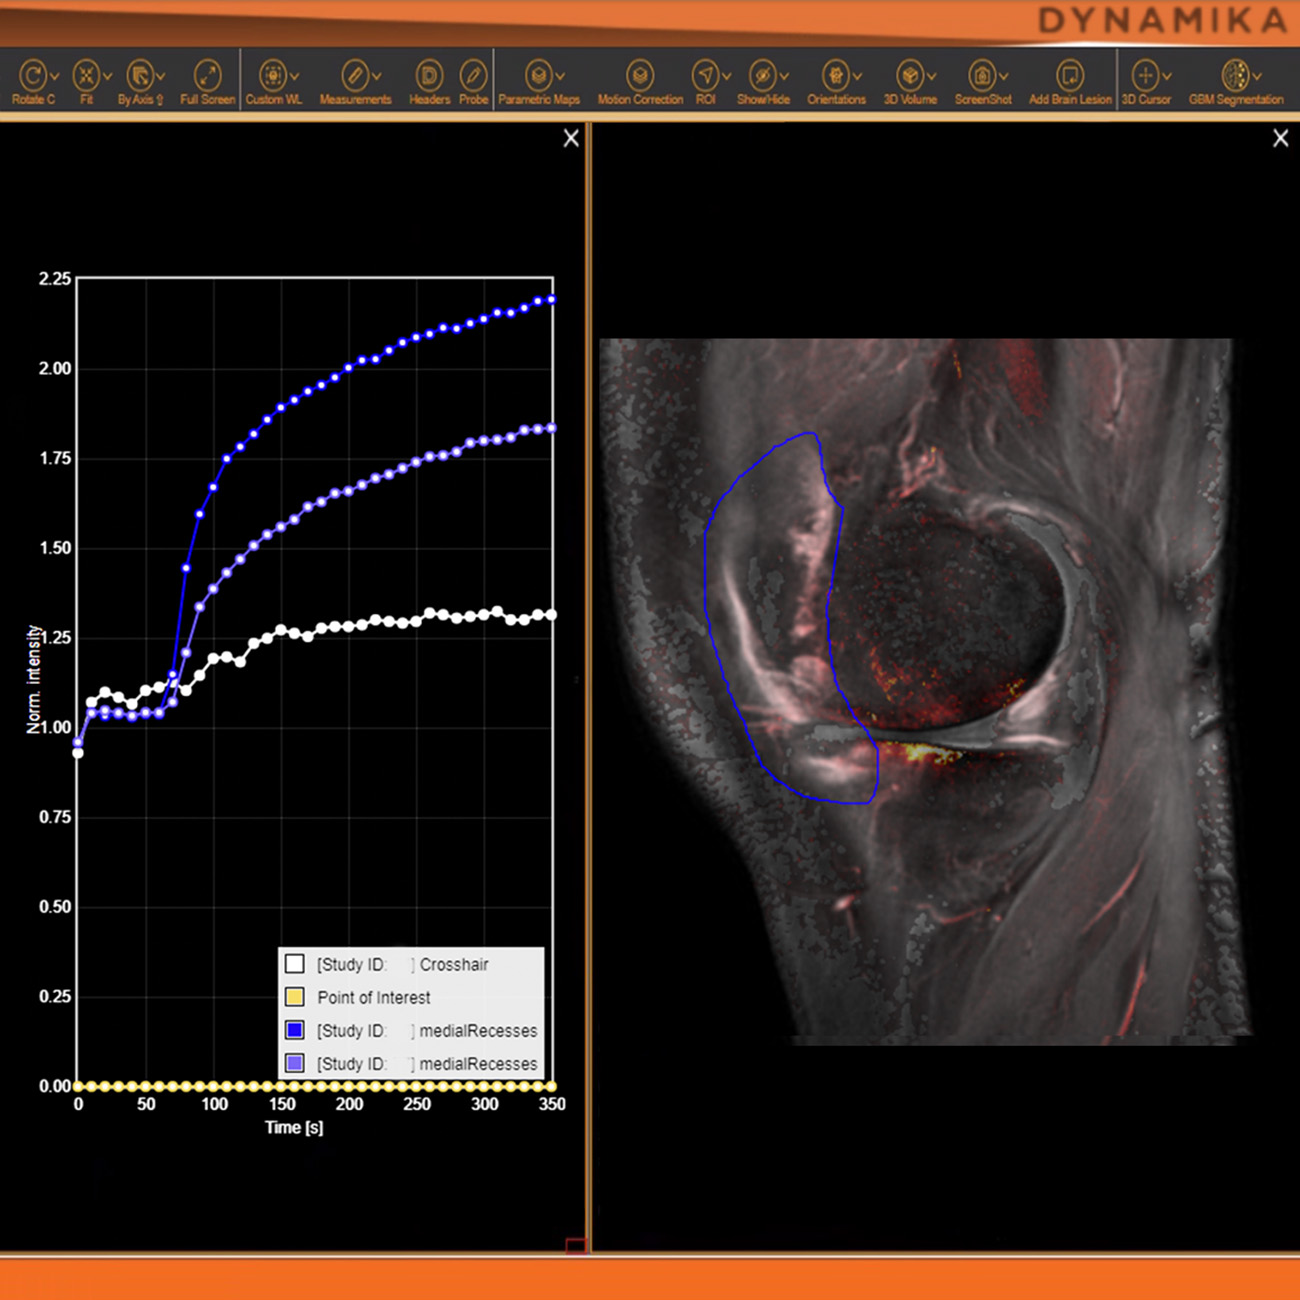

The role of AI in streamlining imaging processes in drug development

Leveraging AI-powered image analysis for enhanced efficacy and safety assessments in clinical trials

Strategies for integrating AI technologies into existing workflows